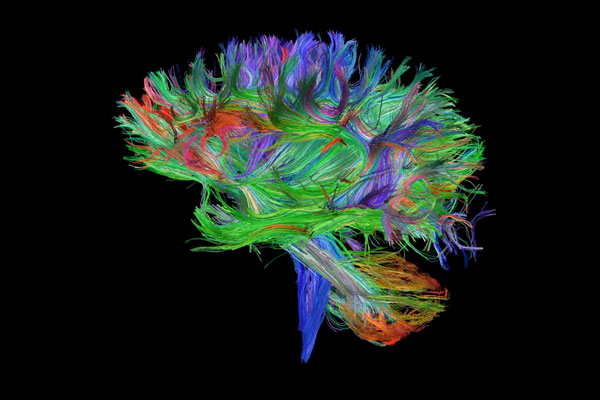

Building Brain Pathways (Video)

Bonus Prize Winner

Brenton Hordacre

School of Health Sciences

This series of images comes from our current stroke study looking at a treatment to enhance recovery of arm function. We use magnetic resonance imaging (MRI) scans to tell us several pieces of information about the brain and how it has been affected by stroke. This particular set of images tells us about the brain’s pathways (the coloured lines). Each of the lines in this image represent an individual brain pathway. We are primarily interested in a bundle of pathways called the corticospinal tract which is the vertical blue/purple lines seen in the video that connect to the spinal cord. This pathway carries commands that control movement of our arms. Having a functional corticospinal tract is an important factor in recovery from stroke.